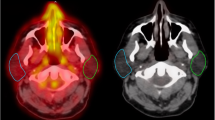

SPECT, MRI and CT were performed separately. For the SPECT scan, we obtained reproducibility of the positioning of the head and neck as during RT by the use of immobilisation mask fixed to the table by adhesive tape. All images and the radiation dose data were transferred for image fusion to our in-house developed workstation for co-registration (Worldmatch Workstation) in DICOM format [20]. Keeping the limitations of the mask fixation in mind, it was decided that for more accuracy, matching was performed on different anatomical regions for different ROIs, e.g. for the analysis of parotid glands or oropharyngeal tumours, the co-registration was done in such a way that it ensured adequate matching for that area only. For co-registration of ROIs in the neck (e.g. lymph nodes or hypopharyngeal tumours), only the neck and vertebral column was used in the matching procedure. Accurate matching of body contours and bone structures was visually verified. SPECT, composite SPECT/SPECT, CT and SPECT/CT images, obtained using a colourwash technique, were simultaneously examined using linked cursor to evaluate Annexin V uptake in tumour and normal tissues.

TAVS imaging co-registered with planning CT scan in frontal plane and axial plane, a and c at baseline, b and d after treatment, from patient number 2. The Annexin uptake is represented by colourwash. In b and d, the isodose lines show the dose distribution in relation to the parotid gland and primary tumour (isodose lines shown, 40, 60, 80 and 95% from outer to inner side of patient). Note the increased treatment-induced Annexin uptake in the right parotid gland, in correspondence to the higher radiation dose distribution, when compared to the left parotid gland. Also note the weak increase in primary tumour Annexin uptake in the right oropharynx after treatment and in the anterior floor of mouth (d)